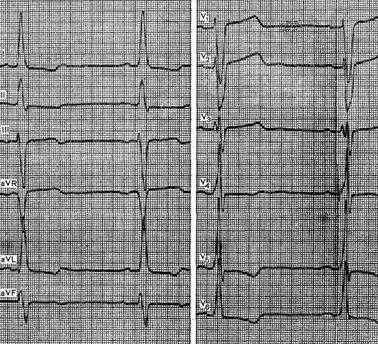

На рисунке представлена ЭКГ больной 35 лет с диагнозом: рак легкого, ревматический митральный порок сердца с преобладанием стеноза. На ЭКГ видны увеличение амплитуды зубца Р в отведениях I и II, отрицательный зубец Р в III отведении, ширина этого зубца превышает 0,11 с. Имеются выраженная отрицательная фаза зубца Р в отведении V1, высокоамплитудные зубцы Р в отведениях V5 и V6.

Все перечисленные признаки свидетельствуют о гипертрофии левого предсердия. Наряду с этим есть несомненные признаки гипертрофии правого предсердия, в частности выраженная положительная фаза зубца Р в отведении V1, высокоамплитудные, заостренной формы зубцы Р в отведениях V2 и V3, глубокие зубцы Р в отведении aVR. Кроме того, на данной ЭКГ имеются признаки гипертрофии правого желудочка: отклонение электрической оси сердца вправо, сдвиг переходной зоны влево, желудочковый комплекс типа qR в отведении V1.